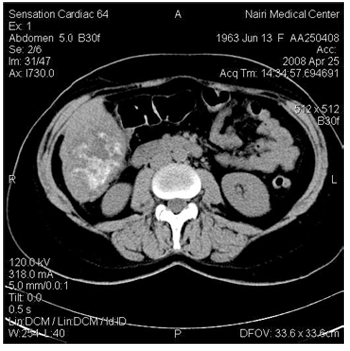

Многослойная КТ с тонкими срезами обычно позволяет решить такие проблемы при поражениях размером более 3-4мм, но может создать новые проблемы, отображая еще более мелкие очаги поражения. Однако сканирование в интерстициальной фазе позволило надежно отличить мелкие кисты от гиперваскулярных опухолей, так как последние в этой фазе выглядят изоденсивными [1.2]. После контрастирования может наблюдаться псевдоусиление (до 10 HU) вследствие частичного обьемного усреднения с окружающей печеночной тканью. Перибилли- арные кисты были множетственные и располагались в воротах печени. У 6 больных при КТ с контрастированием наблюдалось ослабленное кровоснабжение в артериальной фазе, по сравнению с окружающей печеночной тканью. В тех случаях, когда доминировала узловая КТ характеристика опухоли, центральная часть опухоли была гиперденсной, а пери-ферическая область - гиподенсной, как в замедленной (поздняя фаза, фаза вымывания) фазе (рис.2), так и в артериальной фазе (рис.3).

Рис. 2. Контрастусиленная КТ в венозной фазе: многоузловая ГЦК с гиперваскулярной структурой